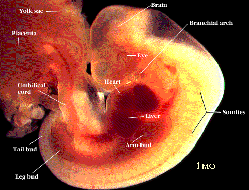

莫勒教授的著作裡在中世紀的標題下:『在中世紀,科學發展得很緩慢,人們對於胚胎學所知很少,而在穆斯林那裡,《古蘭經》卻提到人類的孕育與生長。人是由男女兩性的精液、卵細胞結合而受孕,並在多處指出人由受精卵而孕育,同時闡明了受精卵六天後像一粒種子般地植入母腹中。現今科學已證實了受精卵在著床後開始分化並在六天後開始生長。《古蘭經》也提到了受精卵逐漸生長,變成一團血塊。分裂後的受精卵,很像「阿來格」 (血塊)可以看到那個階段胚胎的外貌類似於「蛹」(如左圖所示)。圖中胚胎與「蛹」或水蛭在外形上沒有什麼二樣,在下一階段胚胎的外貌就像被咬過一口的奶酪或木片,如圖所示。胚胎已具有人的跡象。在過了四十一或四十二天後,胚胎已被認為完全是人的形象了,自此和動物的胚胎已不同了。在該階段胚胎已開始具有人的特徵,就像右圖中所示的樣子。

胚胎的確是在三層暗壁內孕育、生長,這就是(如下圖):

1. 母親的外部腹壁;

2. 子宮壁;

3. 直接包裹著胚胎的胎衣。

母腹中的胚胎有三層暗壁保護著,它們是:1、腹壁;2、子宮壁;3、胎膜(見右圖示)。因為胚胎各階段的生長是十分復雜的,它持續地突變,所以可以運用《古蘭經》、《聖訓》中所提到的術語及其含意建立一套新的胚胎發展階段劃分法,新的體系更簡明、扼要,而且與現代對胚胎發展的新知吻合。